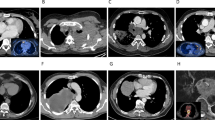

Since we were unable to include matching controls in our scRNA-seq analysis of the five human FFPE samples, we resorted to the PTCL mouse model to gain insights into the transformation process and the differences between tumor and healthy cells. For this purpose, the spleens of two tumor-bearing mice were isolated, and single cells were processed using the 10x Chromium platform. The sequence data obtained were merged with publicly available scRNA-seq data from two control spleens of healthy mice54. In this integrated object, 14,588 single cells were grouped into 24 different clusters, which were then annotated as described above. (Fig. 5A; Suppl. Fig. 9, Supplementary Data S8, 9). A comparison of mouse and human tumors revealed similar proportions of the various cell compartments, e.g., lymphoid populations such as non-malignant T- and B-cells (Fig. 5B). Especially in the latter, however, a large difference to healthy mouse spleens became apparent, in which B-cells accounted for 70% of the total cell number, while this number dropped to 10% and 8% in mouse and human tumors, respectively. At the same time, a significant increase in tumor-infiltrating myeloid cell populations was observed, from 5% in healthy spleens to over 30% and 20% in the mouse and human tumors, respectively. This inverse correlation between the number of B-cells and myeloid cells when comparing WT to PTCL samples is further illustrated by the pie charts in Fig. 5B. We were able to confirm this phenomenon by multiplex immunofluorescence in murine spleen samples. Through a combination of specific antibodies for the tumor cell marker Ezh2, the pan B-cell marker B220/CD45R, and the neutrophil marker Ly6g, a significant decrease of splenic B-cells with a concomitant increase in Ly6g+ myeloid cell infiltration in tumors was revealed (Fig. 5C, D).

A UMAP plot showing 24 clusters of the integrated scRNA-seq dataset from two control spleen samples (WT) and two PTCL-NOSSmarcb1− tumor samples. B Relative abundance of different cell types in murine WT spleens (left), PTCL spleens (middle), and human tumors (right; NB: in order to ensure comparability, the stromal cells were removed before quantification). The pie charts in the lower part show the ratio between B-cells and myeloid cells. C Multiplex immunofluorescence (IF) images of FFPE sections of murine PTCL-NOSSmarcb1− and control spleen samples (WT: upper panels; tumor: lower panels). For better visualization, the white boxed areas (a to f) are enlarged (2.5x; scale bar = 100 µm). DAPI (gray) provides a nuclear counterstain, Ezh2 (yellow) defines malignant cells (Ezh2hi), B220 (blue) is used as a pan B-cell marker (B220+), and Ly6g (pink) as a marker for neutrophils (Ly6g+). D Quantitative analysis of IF images from (C). Four representative regions of interest (ROIs; size: 1500 × 1500 µm) were selected and analyzed for mouse WT and Tumor samples. A Wilcoxon-Mann-Whitney test was calculated to determine if there are differences between WT and Tumor samples for all comparisons (*p = 0.0286). Boxplot settings: middle, median; lower hinge, 25% quantile; upper hinge, 75% quantile; upper/lower whisker, largest/smallest observation less/greater than or equal to upper/lower hinge ±1.5 * IQR. E The heatmap shows the overlap between cluster-specific DEG lists and the cancer hallmark metaprograms. F Signature plots of the programs Cycling, MYC, EMT and Stress in cells from WT (left) and tumor (right) samples. G A split violin plot (left/gray half: WT; right/black half: tumor) illustrates the increase in T-cell exhaustion features (Exhaust.) with a simultaneous decrease in NK cytotoxicity (Cytotox.) markers (e.g., Ncr1/NKp46) as well as infiltration of immunosuppressive myeloid cells in tumor versus WT samples. Source data of B and D are provided as a Source Data file. B Created with BioRender.com released under a Creative Commons Attribution-NonCommercial-NoDerivs 4.0 International license.